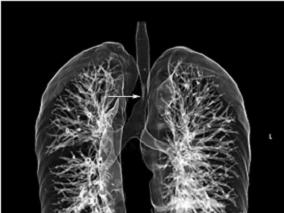

1小时条评论一、病史摘要 患者,男性,27岁,因反复咯血26天于2009年10月5日入院。患者于2009年9月9日修车时突然出现咯血,量约250ml(1~2次),鲜红色,无发热、咳嗽、咳痰、气促及胸痛等不适,就诊于当地县人民医院,胸片示右下肺不张(图120‐1),予以垂体后叶素等药物治...